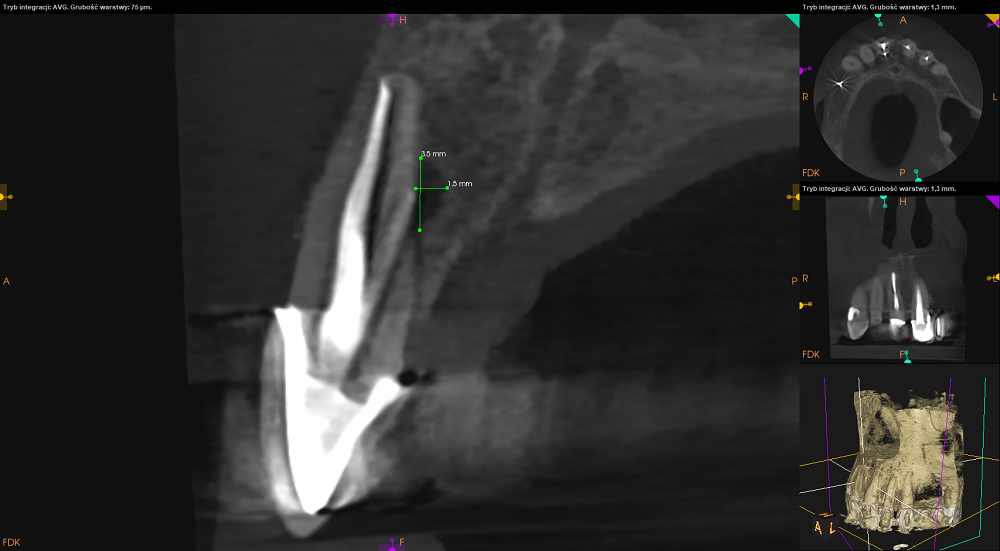

Ząb 11 – przeleczony kanałowo. Odbudowany protetycznie koroną na wkładzie.

Kanał wypełniony na całej swojej długości.

Tkanki okołowierzchołkowe bez widocznych radiologicznie cech patologicznych.

Perforacja korzenia po stronie podniebiennej – zanik tkanki kostnej w projekcji tego miejsca.